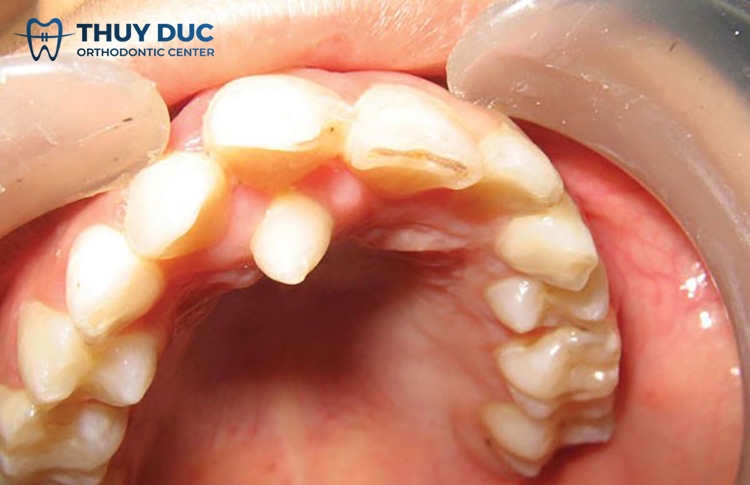

Khiến răng mọc chen chúc, khấp khểnh: Những chiếc răng thừa thường mọc chen vào vị trí của những chiếc răng đã mọc sẵn, đẩy và lấy mất không gian của những chiếc răng này. Điều này khiến cho răng bị nghiêng, thay đổi hướng mọc. Lâu dần sẽ dẫn đến tình trạng răng mọc chen chúc, khấp khểnh rất mất thẩm mỹ.